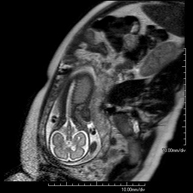

- Foetal MRI

This non-invasive diagnostic procedure uses an electromagnetic field and radio waves (from a transmitter and receiver) to acquire high-definition anatomical images of the foetus in a pregnant woman. It is a radiation-free procedure. It can be performed from week 12 of pregnancy onwards and is safe for both the foetus and the mother. It is used when there is suspicion of some congenital morphological anomaly.